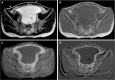

We present a case of a 14-year-old girl, Bacillus Calmette-Guérin (BCG) vaccinated, who presented with vague symptoms of abdominal pain, weight loss, and fatigue. Imaging studies revealed a pelvic mass, later found to be pelvic tuberculosis, a rare diagnosis to consider at this age. The diagnostic approach was difficult, since all investigations pointed strongly to a malignancy, from clinical, imaging (ultrasound and magnetic resonance), laboratory (elevated CA-125), and even macroscopic findings at laparotomy. Histopathology was the first hint (noncaseous granulomata), but the ultimate documentation of Mycobacterium tuberculosis relied on a persistent clinical suspicion, despite contradicting results. Surgical approach could have been mutilating, with irreversible consequences, considering it was a girl with a long reproductive life ahead. Tuberculosis is still a great masquerade, especially the extrapulmonary forms, and although infrequently seen at this age, it should thus be considered in the differential diagnosis of complex pelvic masses in order to avoid surgical iatrogeny/morbidity.